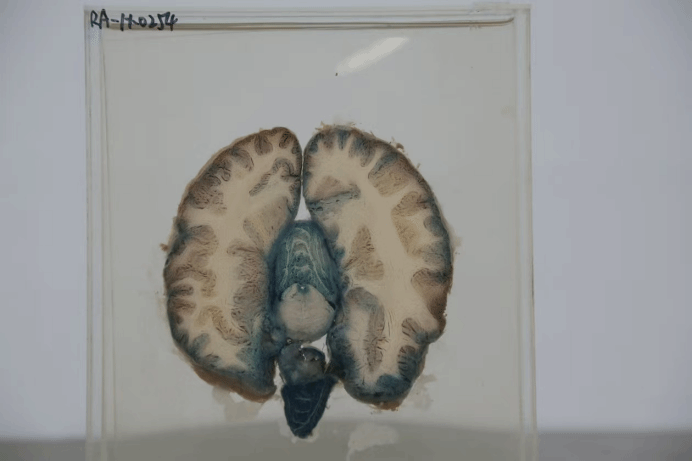

RA-H-0254端脑的水平切面

标本名称:端脑的水平切面标本

解剖部位为端脑,即大脑,此标本展示的是端脑经过水平方向切割后的切面,呈现了大脑半球内部的结构,包括大脑皮层、皮层下白质、基底核以及部分脑室系统等结构。